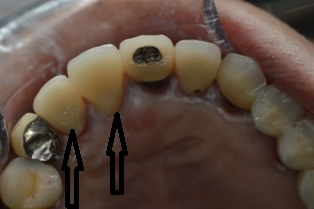

2014年7月16日 / 最終更新日時 : 2019年5月17日 まえだ歯科 ブログ 美しいジルコニアクラウン 術前(矢印はジルコニアクラウン) 術後(矢印はジルコニアクラウン) お口の中をジルコニアで修復していくと、白い歯がふえていって、美しいですね。ツルっとした舌感も気持ちいいようです。 歯科医師 前田